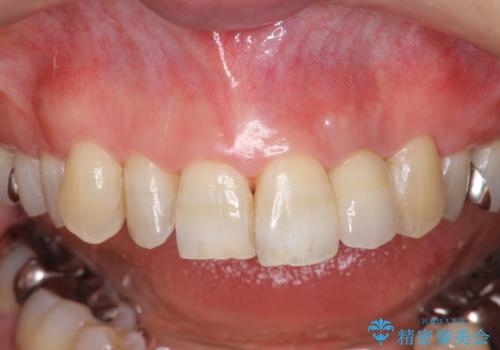

自然な色調のクラウンが製作され、審美障害が改善し喜んでいただくことができました。

- 15.4万円(ジルコニアクラウン・仮歯・ファイバーコア)費用は治療当時の料金となります